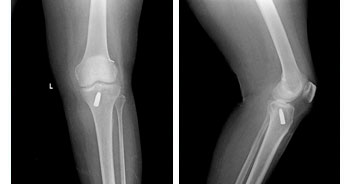

Knee and Hip replacements surgeries are routinely done in this hospital under different categories and Packages. Joint replacement team is headed by Dr.P.Elangovan M.S, Mch Ortho, who has more than 1000 joint replacement surgeries to his credit and is a vastly experienced surgeon and uses both European and American implants. Staggered bilateral knee replacement is the standard practice in this hospital.

• Total Knee Replacement